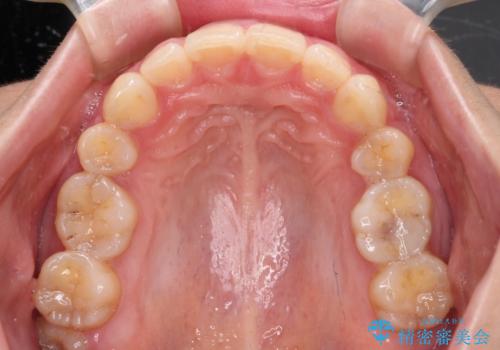

上顎前突 目立たないワイヤー装置での抜歯矯正

左右ともに下顎に対して上顎歯列が前方位にある上顎前突であったので、上顎歯列全体を後方に移動させることで上下咬み合わせを改善し、その上で抜歯矯正により口元の突出感を改善させていきました。

- 口元の突出感改善を希望して来院された患者様です。

口元を積極的に引っ込めるために、上下左右の小臼歯計4本を抜歯することとしました。

咬み合わせが深いため、咬み合わせの高さを向上させながら口元を下げることとしました。